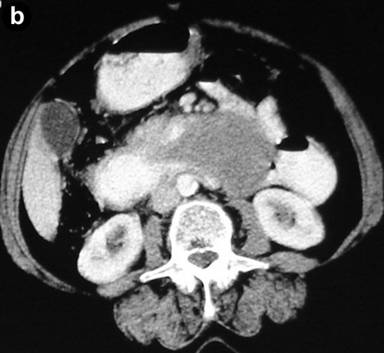

Abdominal ultrasonography showed a distended gallbladder without any calculi, prominent intrahepatic biliary radicals, a (10 mm) common bile duct dilated to the lower end with no calculi, prominent main pancreatic duct and a 2.8x1.9 cm hypoechoic mass near the distal end of the common bile duct. An abdominal computed tomography (CT) scan confirmed the dilatation of the common bile duct and the main pancreatic duct, and revealed an ill-defined hypodense mass 6.5x5.5 cm in size arising from the uncinate process of the pancreas (Figure 1). The mass involved the duodenum with an extension to the duodenojejunal flexure. The proximal duodenum was found to be dilated. The CT scan suggested the diagnosis of a pancreatic mass with duodenal infiltration. Upper gastrointestinal endoscopy was performed showing esophagitis and extraneous compression in the duodenal bulb. A side view endoscopy was performed and showed a long pedicle-like structure extending from the duodenal bulb into the distal duodenum along the medial wall of the second part of the duodenum (Figure 2). The distal end of this structure, the ampulla and the distal duodenal lumen could not be visualized. An attempt was made to pull the distal end of the structure using biopsy forceps but without success. Besides these findings, no ulcers, strictures or growths were found in the duodenum. In view of the endoscopic findings, the CT scan was again reviewed. The mass initially described as originating from the uncinate process was suspected to be intraluminal within the distal duodenum with a smooth outline at the distal end. However, this mass could not be defined as separate from the pancreas. In addition, a characteristic sign of “duodenal wall invagination” was observed in the dilated first part of the duodenum (Figure 3). Barium meal examination of the upper digestive tract showed a well defined smooth lobular filling defect in the dilated first part of the duodenum (Figure 4). Given the above findings, a duodenal polypoid mass of unknown nature was suspected. A side view endoscopy was repeated and endoscopic ultrasonography (EUS) was also performed. During this examination, a large polypoid mass with normal overlying mucosa was seen in the proximal duodenum (Figure 5a). The ampulla was seen as separate from the polyp and was found to be normal as was the visualized distal duodenum (Figure 5b). Endoscopic ultrasonography revealed a homogenous echogenic mass occupying the submucosa in the duodenal bulb with a normal pancreas which was not involved by the mass (Figure 5c). A biopsy taken from the polyp showed non-specific changes in the mucosa.

Figure 1. CT scan showing hypodense mass involving the distal duodenum and the uncinate process of the pancreas, and extending to the duodenojejunal flexure (arrow), causing dilatation of the proximal duodenum. |